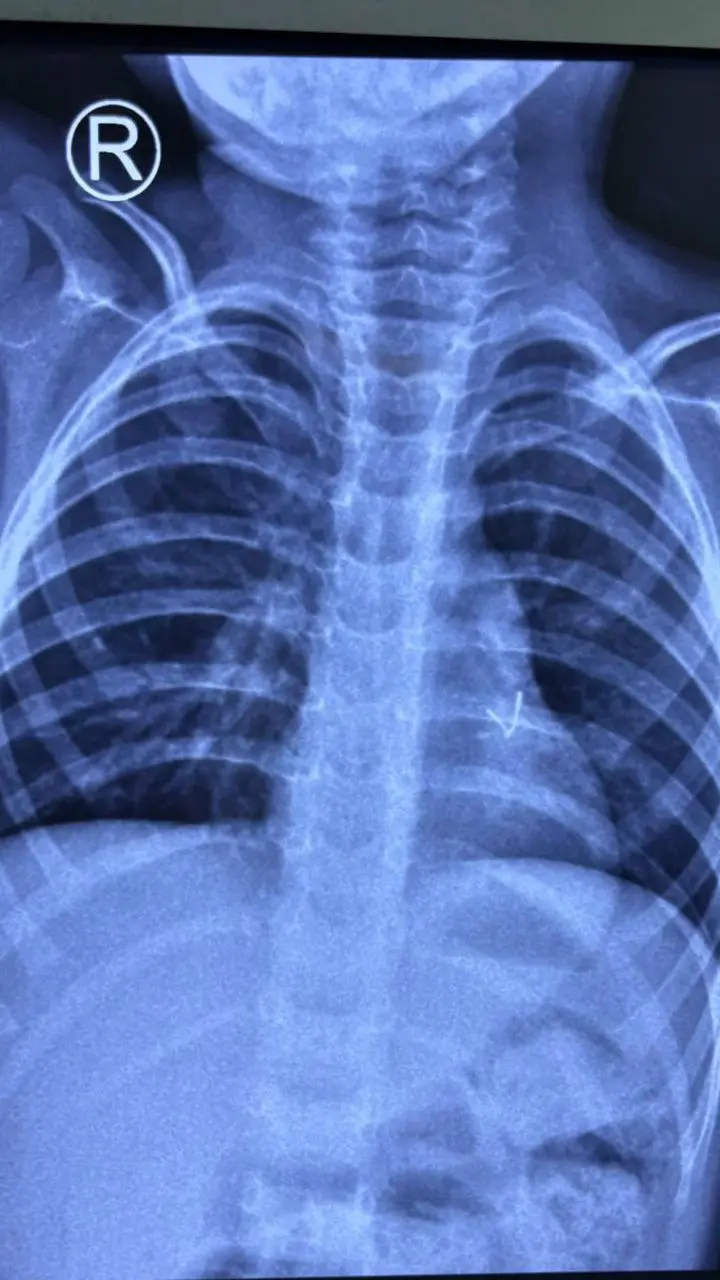

اس تصویر میں بچے کے پھیپھڑوں کے آخر میں ایک سفید دھبہ نظر آتا ہے، جو کھلونا گاڑی کا بلب ہےچھوٹے بچوں کے ہاتھ جو لگتا ہے وہ عموماً اسے نگلنے کی کوشش کرتے ہیں اور یہی بات بہت سے والدین کو فکرمند رکھتی ہے۔

جب تین سالہ راہل کی طبعیت کچھ خراب ہوئی تو ابتدائی طور پر ڈاکٹروں نے انھیں نمونیا کی تشخیص کی اور اُن کے علاج کے لیے اینٹی بائیوٹک ادویات بھی تجویز کی گئیں۔

مگر طویل علاج کے باوجود بچے کی طبعیت نہ سنبھلی، جس کے بعد ڈاکٹروں نے بچے کے سی ٹی سکین سمیت تفصیلی معائنے کا فیصلہ کیا۔

تفصیلی جسمانی معائنے کی ابتدائی رپورٹ میں بچے کے ایک پھیپھڑے کے بائیں جانب دھات کا ایک ٹکڑا نظر آیا جسے بذریعہ آپریشن نکالنے کا فیصلہ کیا گیا۔